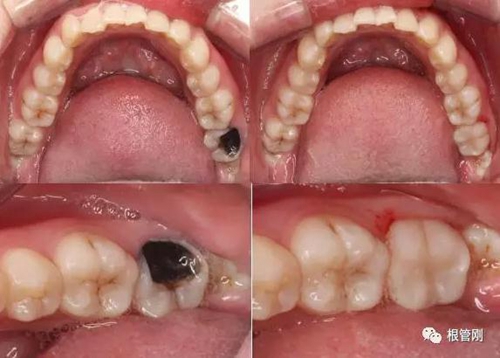

這是一顆嚴重的蛀牙,顏色發(fā)黑,牙齒的一半已經(jīng)崩解,看到此情此景,也許很多人會想它的神經(jīng)肯定死掉了吧?它還有救嗎?應該會做根管治療+牙冠修復吧?

經(jīng)細致的詢問病史(有沒有自發(fā)痛,冷熱刺激敏感等)、仔細的檢查(包括探診,冷診,熱診,叩診以及牙片的檢查不可缺少),綜合各種信息判斷,得出準確的診斷為深齲,在與患者溝通,患者同意直接樹脂修復!

顯微鏡下非常精確與清晰的去凈齲壞組織,精細的操作盡最大程度保留剩余健康牙本質(zhì),這也需要醫(yī)生精湛的技術!